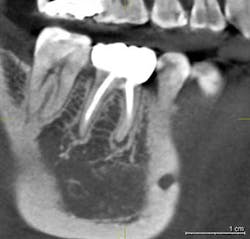

Our implant consultation begins with collecting all the necessary patient information, required legal notices, HIPAA release, etc. Following the initial patient registration, the patient is escorted to our in-house cone beam CT scanner to obtain a full-mouth 3D CBVCT. I highly recommend a full-mouth scan for multiple reasons. First, I believe in comprehensive examinations and diagnoses. As an oral health-care provider, I am responsible for all structures between the left and right buccal mucosa, oral labial mucosa to oral pharynx, and floor of the tongue to the palatal gingiva. I perform an oral cancer screening, full-mouth periodontal probing, and require full-mouth radiographs for all new patients, regardless of the chief complaint or reason for referral. The full-mouth radiographs are required for a comprehensive diagnoses, and I satisfy this requirement with any of the following: Panoramic X-ray, FMX, or full-mouth CBVCT. I can’t tell you how many asymptomatic periapical lesions or severe periodontal bone loss I have seen on CBVCTs that were not otherwise detectable, but that’s another conversation for another time.

Asymptomatic periapical radiolucency found in the opposite arch of planned implant.